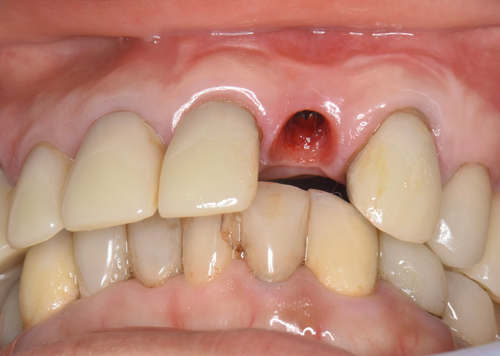

唇側の半分がほとんど骨が失われていました。この状態からインプラントを移植して、不足している骨も同時に再生定着

させていきます。

増設した人工の骨をより定着させるために、血液から作ったコラーゲン膜を何層にも敷き詰めていきます(無料)。あとは仮歯を施して、骨が固定するのを6ヶ月間待ちます。

①抜歯と②インプラントの移植と③欠落した骨の再生の3つを1日で完結させました。通常なら2年近くかかる治療内容を当院では半分で終わらせる事に注力しています。